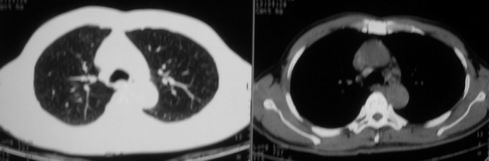

男,62岁,咳血两天。无其他不适。

片状磨玻璃影,考虑肺泡出血可能性大,其他不排除,建议hrct

右上磨玻璃样密度影,考虑就是个肺泡出血,别的没有

病灶呈“磨玻璃影”,较薄,周围无卫星灶,很难一口说是肺结核,建议积极治疗后,短期复查!(支持考虑:肺泡出血!)

右肺上叶可见多发磨玻璃状影,符合肺泡内出血表现,严格意义上讲应该是肺泡内积血。引起出血的原因很多,不一定非得结核所致。